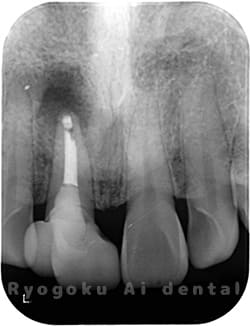

Case02

-

- 原因

- 慢性根尖性歯周炎

- 治療期間

- 1回(消毒・洗浄も含めると3回)

- 治療内容

- 歯根端切除術

- 治療費用

- ¥110,000

他院で抜歯と判断され、インプラント治療を提案された患者様です。被せ物を外さずに、歯の根尖部に外科的にアプローチし、病気の部分を除去しました。

<リスク・副作用>

外科手術のため、術後に出血、痛みや腫れ、違和感を伴います。口腔内の状態によっては適応できないことがあります。歯根端切除で治らなければ抜歯を検討しなくていけない場合もあります。